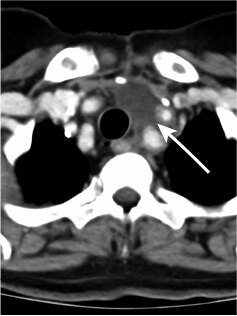

淋巴管畸形

李威醫(yī)生的科普號2023年10月07日276